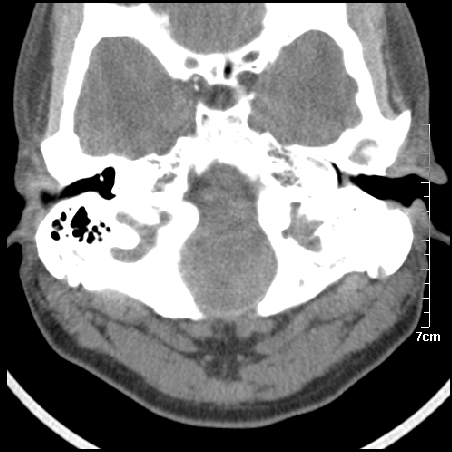

病例1

m/46y 头晕.耳鸣半月余 有乳突炎病史

病例2

m/27

左侧板障型乳突。

左侧慢性中耳炎伴胆脂瘤形成。